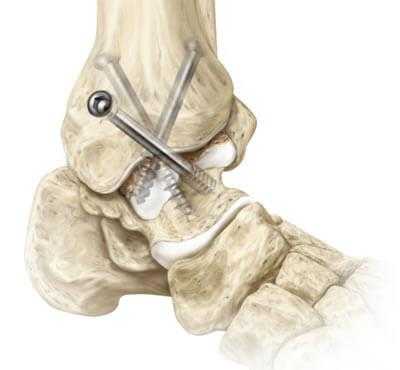

Артродез голеностопного сустава - оперативное вмешательство по искусственному сращению сочленяющихся суставных поверхностей голеностопа в физиологически выгодном для функционирования ноги положении. Основной целью хирургического лечения является придание опоропрочности проблемной зоне посредством полного блокирования ее подвижности (создания анкилоза). Обездвиживание достигается за счет жесткого соединения примыкающих концов костей сустава между собой специальными фиксаторами из металла (спицами, винтами, штифтами и пр.). Это позволяет прочно срастись суставным поверхностям друг с другом под нужным углом, то есть, привести сочленение в полное неподвижное состояние, что поможет пациенту избавиться от сильной боли и нестабильности стопы.

- Внутрисуставный. В процессе хирургии выполняется вскрытие капсулы сустава с последующим удалением поврежденного гиалинового хряща с поверхностей костных элементов. После репозиции костей в выгодном положении выполняется их фиксация металлическими приспособлениями.

- Дальше стопа выводится из порочного положения. Большеберцовый элемент и таранный компонент плотно сопоставляют друг с другом в удобной с точки зрения физиологии позиции. Достигнутая позиция скрепляется металлической конструкцией необходимого типа.